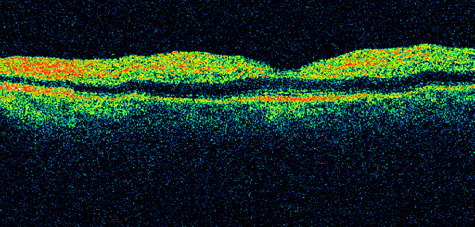

CENTRAL RETINAL ARTERY OBSTRUCTION Central retinal artery obstruction is one of the most sudden and dramatic events seen by ophthalmologists and was described as early as 1859.1 Although there have been numerous clinical and experimental studies of the pathophysiology of central retinal artery obstruction and although these studies have been augmented by the introduction of intravenous fluorescein angiography in the 1960s, the disease still has a relatively poor visual prognosis. The clinical picture is typically striking. Patients present with a sudden painless loss of vision. The appearance of a cherry-red spot in the fundus is characteristic (Fig. 1).2 The cherry-red spot appears because soon after obstruction of the blood flow to the inner retina, the normally transparent retina becomes opaque and blocks the brownish-red color from the underlying choroid, which is still supplied by blood. Because the retina overlying the foveola is relatively thin, however, the normal color of the choroid is still visible in this area.3,4 Although characteristic, the cherry-red spot is not pathognomonic for central retina artery obstruction.5 Sometimes the characteristic cherry-red spot does not develop; there may be only a slight accentuation of the brownish-red color in the foveola.4 It is not known how long it takes this cherry-red spot to appear, but in a primate model, it has appeared as early as 30 minutes after obstruction.6 An afferent pupil defect is usually present.2 With obstruction, virtually all eyes have narrowing and irregularity in the arteries and there is frequently an irregularity in the caliber of the retinal veins.2,4,6,7 Segmentation (boxcarring) of the blood column frequently develops; this segmentation is particularly noticeable in the veins and can be seen as a to-and-fro movement of the blood elements.3,4 Retinal hemorrhages, however, are not characteristic of central retinal artery obstruction.7 With time, the retinal opacity diminishes, generally leaving an optic nerve that is atrophic (Fig. 1). Frequently, thinned retinal arteries and veins also remain.7,8 No foveolar light reflex is evident, and a finely pigmented appearance of the macula is typical.7 In some cases, arterial collaterals develop at the optic disc.9–11 Rarely, anatomoses that exist between the central retinal artery and the ciliary arteries become visible as preretinal loops (Nettleship collaterals) after an occlusion at the edge of the disc.12,13,378In approximately 20% of patients, an embolus is evident somewhere in the arterial system.14 Emboli are discussed later. Intravenous fluorescein angiography is useful in showing the details of the abnormal circulation of a central retinal artery obstruction (Fig. 1). The principal abnormality is the delay in the appearance of the dye in the central retinal artery and its branches.2 Rather than the central retinal artery and its branches filling rapidly, considerable time may elapse before the entire arterial system is filled.15 The filling of the retinal arteries is often abnormal, with the fluorescein partially filling an artery (a dye front) or hugging the vessel wall, as in normal venous filling.15 Segmentation of the blood column is often well defined on fluorescein angiography.15 Venous filling is usually slowed and occasionally the dye does not progress beyond laminar flow during the study.14 In approximately 10% of eyes that have central retinal artery obstruction, there are abnormal choroidal filling defects, reflecting posterior circulation obstruction. These defects can occur even in patients who appear to have a typical central retinal artery obstruction.14 Leakage of dye from the vessel walls is not normally seen except at the site where an embolus lodges within a retinal artery.16 With time, the flow within the artery and its branches is reestablished and the appearance of the intravenous fluorescein angiogram may return to normal. The electroretinogram (ERG) is usually abnormal in central retinal artery obstruction. The b-wave is reduced, indicating a marked abnormality in the circulation of the inner retina.17,18 The a-wave, indicating normal photoreceptor function, is preserved or accentuated. There does not appear to be a good correlation, however, between the extent of b-wave abnormality and the degree of retinal function,3 although Yotsukura and Adachi-Usami420 reported that the b-wave amplitude increased with visual improvement. The photopic negative response (PhNR) shows severe depression in this condition reflecting the significant loss of the ganglion cells and their axons.377 The electrooculogram may be either normal or abnormal. Visual field defects are usually profound but either occasionally a small portion of the temporal peripheral visual field remains or the patient has a large central scotoma.3 The onset of obstruction occurs most often between the hours of midnight and 6 AM, with the second most common period being between 6 AM and noon.2 Most patients with central retinal artery obstruction complain of a sudden loss of visual acuity in the affected eye; most of these patients present with visual acuity ranging from finger-counting to light perception.14 Only about 5% of patients have visual acuity of no light perception and most of these have involvement of the posterior ciliary circulation, which can be seen on either intravenous fluorescein angiography or electrophysiology.14 Without a partial central retinal artery obstruction or a spared cilioretinal artery (to be discussed), it is unlikely that any patient will have initial visual acuity better than finger-counting.14 With or without treatment, most eyes retain visual acuity of finger-counting to light perception. Patients with a spared cilioretinal artery do not seem to have a follow-up visual acuity that is significantly different from those without a spared cilioretinal artery.14 Central retinal artery obstruction is caused by the disruption or cessation of blood flow to the central retinal artery, its branches, and the retinal layers supplied by those vessels. The inner two thirds of the retina derives its blood supply from the central retinal artery and its branches; the outer third of the retina is supplied from the choroidal circulation.19–21 The central retinal artery and its branches function as an end artery, and with the exception of a few anastomotic connections between the retina and the ciliary circulation at the optic disc, there are no other anastomoses.19 No intrinsic retinal vessels are present in the fovea because the inner retinal layers are not present in this area.19 Histopathologically, when a central retinal artery obstruction occurs, the retina initially becomes edematous. With time, all the retinal layers supplied by the central retinal artery and the artery's branches, including the nerve fiber layer, ganglion cells, inner plexiform layers, and the inner portion of the inner nuclear layer, are lost.20 In trypsin digest preparations after obstruction of the central retinal artery, the greatest change is in the capillary bed,22 where extensive ischemic changes take place. Usually, little attempt is made to repair the retina with gliosis or neovascularization.20 The most common site of obstruction of the central retinal artery is at the level of the lamina cribrosa.20 Clinically, it is possible to examine the blood flow velocity in the central retinal artery in a noninvasive manner, using a variety of techniques.21 The most useful appears to be color Doppler imaging, providing simultaneous Doppler and B-scan ultrasound images of the optic nerve head, which primarily represents flow in the central retinal artery.23 Studies using this technique demonstrate a marked reduction of or no blood flow in the central retinal artery with an acute central retinal artery occlusion that returns to normal with time.24 Characteristics of the retinal blood flow can be measured clinically with retinal Doppler velocimetry.385 This is an instrument that can measure the blood column diameter, the centerline blood velocity, and the blood flow in major retinal vessels. However, when evaluating the blood flow in the optic nerve, choroidal, and retina, the Doppler laser flowmetry is more sensitive to the blood flow in the superficial layers than in the deeper layers.410 Masaoka and colleagues384 studied the hemodynamic changes in the retinal circulation with a scanning laser ophthalmoscope and intravenous fluorescein angiography. This technique allows the assessment of erythrocyte velocities and movement with high resolution continuous images and is a useful technique for the evaluation of hemodynamic changes in vascular occlusions. Analysis of the retinal nerve fiber layer by one of the confocal laser scanning tomography techniques can provide information about a central retinal artery occlusion. Foroozan and co-workers383 studied patients with a central retinal artery occlusion within 1 week of occlusion with a scanning laser polarimeter. Diffuse attenuation of the retardation of the nerve fiber layer surrounding the optic nerve was seen in all eyes studied. Four patients were scanned in follow-up at intervals ranging from 1 week to 6 weeks; all had unchanged studies.383 Optic coherence tomography (OCT) of an acute central retinal artery occlusion shows a slight increase in the thickening of the retina and reflectivity of the inner layers of the retina that correspond to the opacity seen clinically (Fig. 1).409 With time, the disc becomes atrophic and the retina thinner. Experimental studies of central retinal artery obstruction in the cat25 and the rhesus monkey26–28 have increased our understanding of arterial obstruction. The most clinically relevant finding is that there is a period in which a total lack of blood flow (ischemia) to the inner retina can be tolerated; that is, if the blood flow is not obstructed longer than this period, visual function may return to normal. This critical time in the cat eye is 90 minutes,25 and in the young, healthy rhesus monkey it is 100 minutes26–28—any longer than this and the histologic changes are irreversible and the animal has permanent visual loss. Hayreh and co-workers379,380 have repeated this experiment to determine how long the retina can survive central retinal artery occlusion in middle-aged and elderly rhesus monkeys, a situation that might be more applicable to the human situation where most occlusions occur in older patients. That study showed that an occlusion of less than approximately 100 minutes produced no permanent damage and that an occlusion of longer than 240 minutes produced massive and irreversible retinal damage. It is not known why the older monkeys had a longer retinal survival time with occlusion of the central retinal artery than younger monkeys. Because there is no evidence that the monkey and the human have different retinas,379 the studies by Hayreh and co-workers have implications for studies that attempt to treat central retinal artery occlusion. Any treatment of this condition will almost certainly have to be initiated within 100 to 240 minutes, assuming the occlusion is total, or the patient will likely have permanent damage to the retina, regardless of treatment. On average, central retinal artery obstruction occurs in patients who are in the fifth or sixth decades of life, with the age range varying from 17 to 84 years. Fewer than 10% of patients are younger than 30 years of age.14,29,30 In some cases, the cause of central retinal artery obstruction is relatively clear, such as when due to a visible embolus. In other cases, however, especially when found in association with a systemic disorder such as diabetes, the association is less clear. Table 1 lists some of the conditions associated with central retinal artery occlusion. Arteriosclerosis is probably the most commonly associated systemic condition. With the progressive buildup of subendothelial atheromatous material, the lumen of the central retinal artery becomes narrowed over time and eventually may become occluded.20 This association is inferred because most patients with central retinal artery obstruction are in the fifth to sixth decades of life, when atherosclerotic changes are expected. TABLE 1. Conditions Associated With Retinal Arterial Obstructions